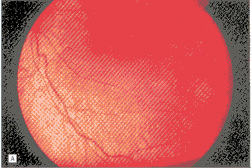

温热治疗时平均的肿瘤基底直径为3.0mm(中位数2.0mm,范围0.2-18.0mm),肿瘤的厚度为2.0mm(中位数2.0mm,范围0.2-6.3mm)(图1)。肿瘤边缘到视盘的最短距离平均为6.0mm(中位数6.0mm,范围0-23mm),到中心凹的最短距离平均为7.0mm(中位数6.0mm,范围0-24mm)。11例(14%)患者伴有视网膜下液体。视网膜母细胞瘤不伴有活动性视网膜下和玻璃体播散。

图1 1例2个月女婴,双眼家族性视网膜母细胞瘤。A,左眼中心凹颞下微小的视网膜母细胞瘤。B,温热治疗1年后随访,肿瘤消退成萎缩斑。中心凹完整,尽管在双眼共有16个肿瘤,全部经单独温热治疗,不需要化疗和外照射放疗